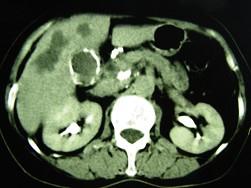

问题 女,66岁,右上腹痛,发热伴有黄疸两月余,消瘦、纳差,影像检查如图,最可能的诊断是()

选项 A.慢性胆囊炎及局灶性脂肪肝 B.胆囊壁钙化及肝血管瘤 C.胆囊癌肝转移 D.肝内胆管细胞癌 E.胆囊癌及原发性肝癌

答案 C